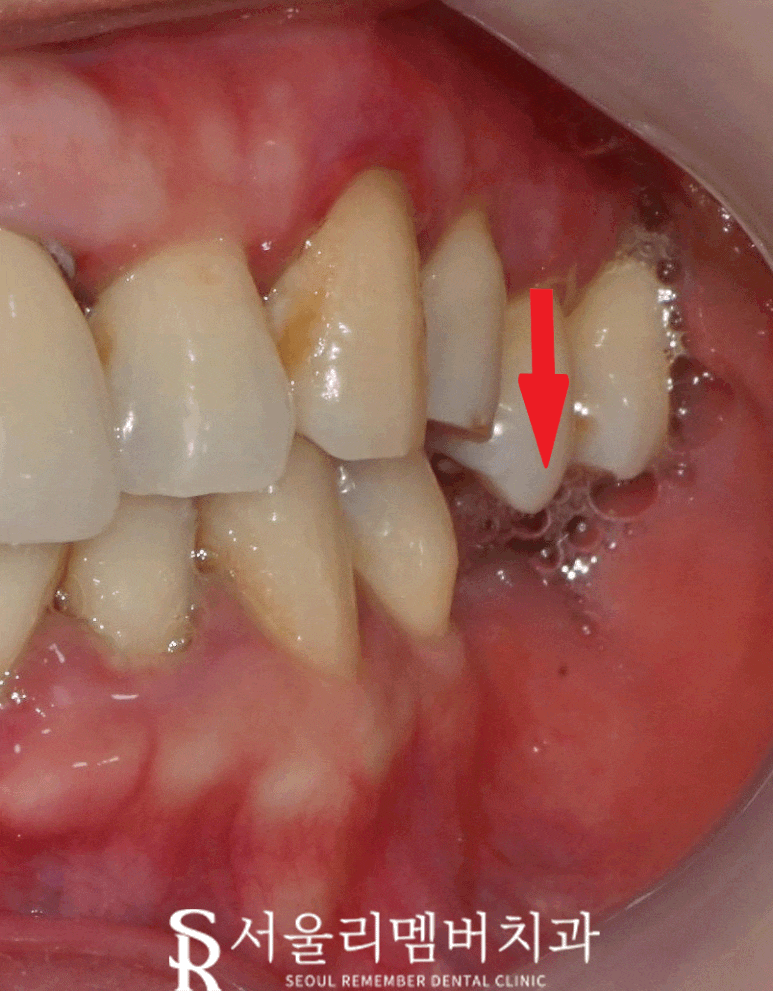

구강 카메라로 찍어 진단 시작하겠습니다.

육안으로 보기에

잇몸 부근이 거뭇거뭇한 게

치태나 치석이 많이 쌓여있고

양쪽 아래쪽 어금니들이 없는 걸

관찰할 수 있습니다.

한쪽을 자세하게 보면

대합치가 빈 곳을 향해 정출된 것을 볼 수 있죠.

착색도 심하여 스케일링 받은 지

오래됐다는 것을 알 수 있었습니다.

관리가 안 된 구강입니다.